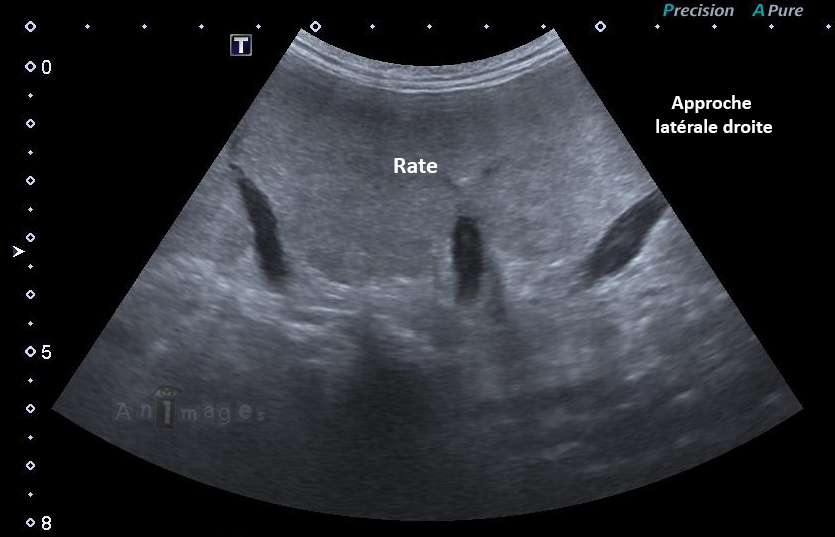

Approche latérale droite